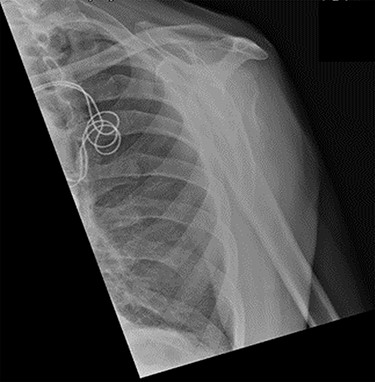

Review at 6 weeks post-injury demonstrated both clinical and radiological healing (Fig. 7). At a final 14-week review, the patient informed that he had returned to playing golf with no adverse symptoms. Examination revealed complete soft tissue healing over the fracture site and the range of movement was recorded as 120° of both abduction and forward flexion. Plain radiographs confirmed excellent fracture union, and the patient was discharged (Fig. 8).

Lateral scapula (Y) view X-ray taken 6 weeks post-injury showing radiological healing of the fracture.